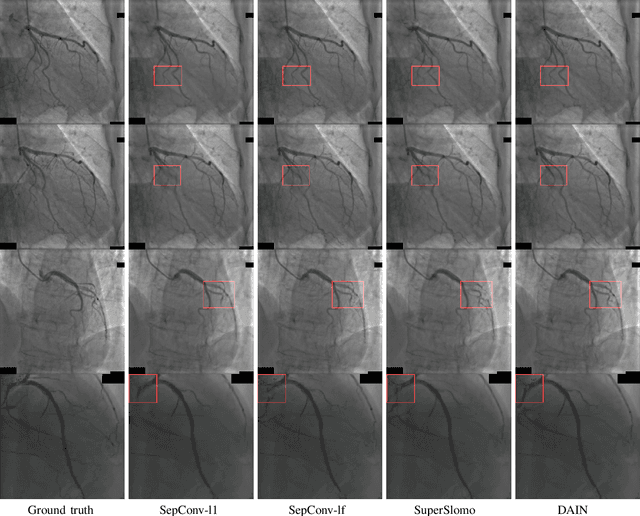

Abstract:Cardiac coronary angiography is a major technology to assist doctors during cardiac interventional surgeries. Under the exposure of X-ray radiation, doctors inject contrast agents through catheters to determine the position and status of coronary vessels in real time. To get a coronary angiography video with a high frame rate, the doctor needs to increase the exposure frequency and intensity of the X-ray. This will inevitably increase the X-ray harm to both patients and surgeons. In this work, we innovatively utilize a deep-learning based video interpolation algorithm to interpolate coronary angiography videos. Moreover, we establish a new coronary angiography image dataset ,which contains 95,039 triplets images to retrain the video interpolation network model. Using the retrained network we synthesize high frame rate coronary angiography video from the low frame rate coronary angiography video. The average peak signal to noise ratio(PSNR) of those synthesized video frames reaches 34dB. Extensive experiment results demonstrate the feasibility of using the video frame interpolation algorithm to synthesize continuous and clear high frame rate coronary angiography video. With the help of this technology, doctors can significantly reduce exposure frequency and intensity of the X-ray during coronary angiography.